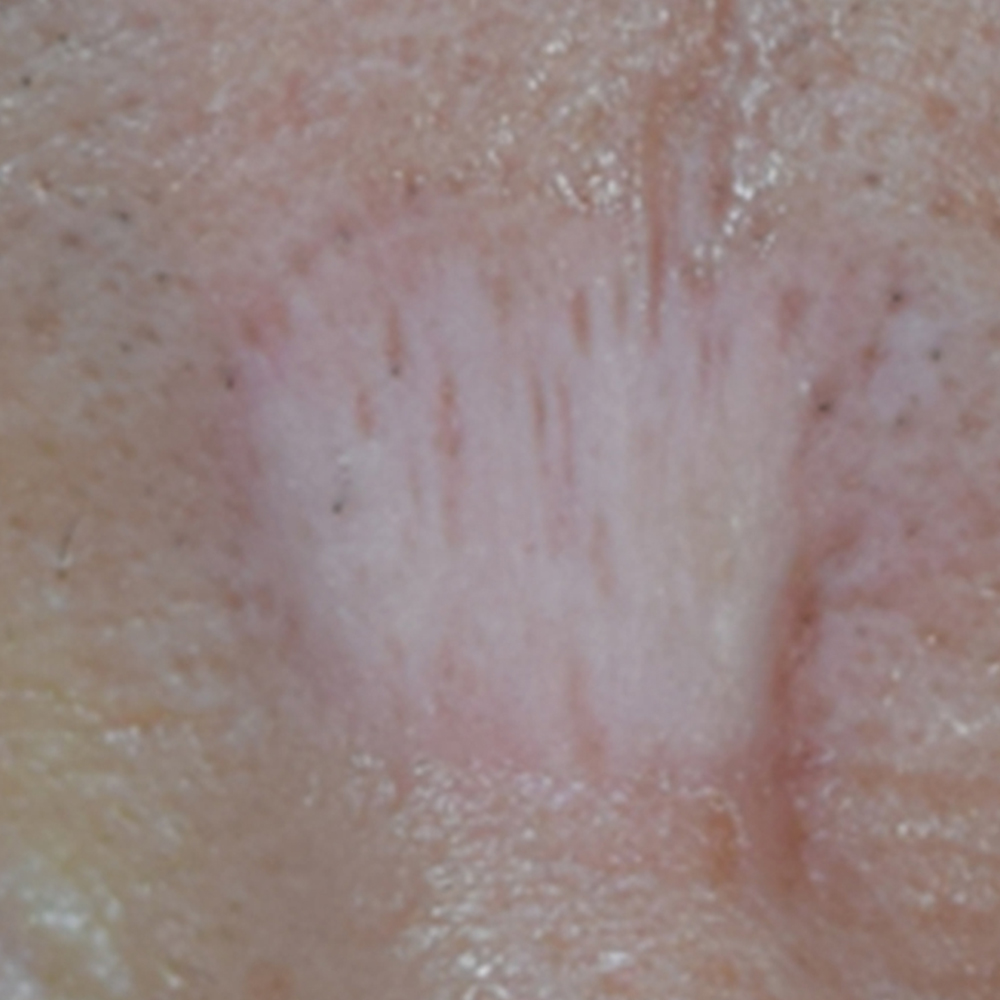

내원 당시 환자분의 사진입니다.

위 환자분은 미간 부위에 오랫동안 자리 잡은 넓은 흉터로 인해 정말 오랜 시간 고민하다가 우리 병원을 찾아오셨다고 하는데요.

사진에서 보이는 것처럼 흉터 부위는 피부색보다 더 하얗게 고착되어 있어, 빛이 닿으면 주변 피부와 대비가 더욱 뚜렷하게 드러나는 상태였습니다.

특히 미간은 표정 근육의 움직임이 많은 부위라 흉터가 더 눈에 띄고, 타인과의 대화 시 시선이 바로 닿는 위치여서 환자분은 심리적인 불편감을 크게 호소하셨고요.